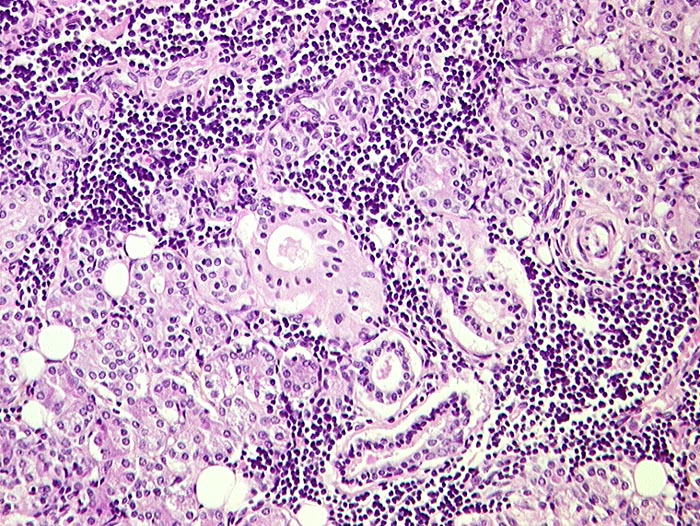

Das Zellbild ist je nach Stadium mehr oder weniger zellreich und zusammengesetzt aus Lymphozyten, Myoepithelien und selten Azinuszellen. Ein lymphozytäres Zellbild ist in Kombination mit dem typischen klinischen Bild (Keratokonjunktivitis sicca, Xerostomie, rheumatische Erkrankung) für die Sicherung der Diagnose ausreichend. Auf die Lippenbiopsie kann in diesem Fall verzichtet werden.